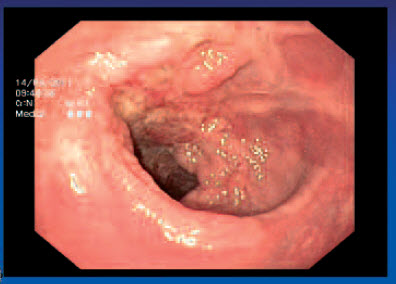

Tumor T2 N1 - kolonoskopie

Tumor T3 N0 - kolonoskopie